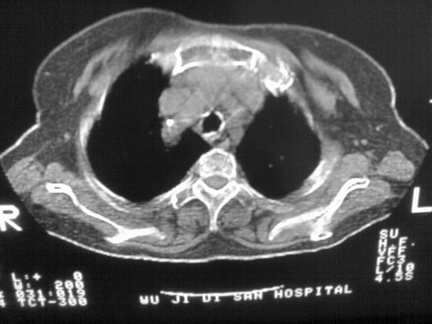

标题: CT13142:女 80 胸闷、气短、1w [打印本页]

标题: CT13142:女 80 胸闷、气短、1w

右肺炎性变

气管,支气管软骨钙化。

右肺感染;双侧胸腔少量积液,心影增大,可能与心功不全有关;胸内甲状腺肿。

胸内甲状腺肿;右肺感染;双侧胸腔少量积液。

胸内甲状腺肿;右肺中叶感染;双侧胸腔少量积液;心影增大,考虑有心功能不全。